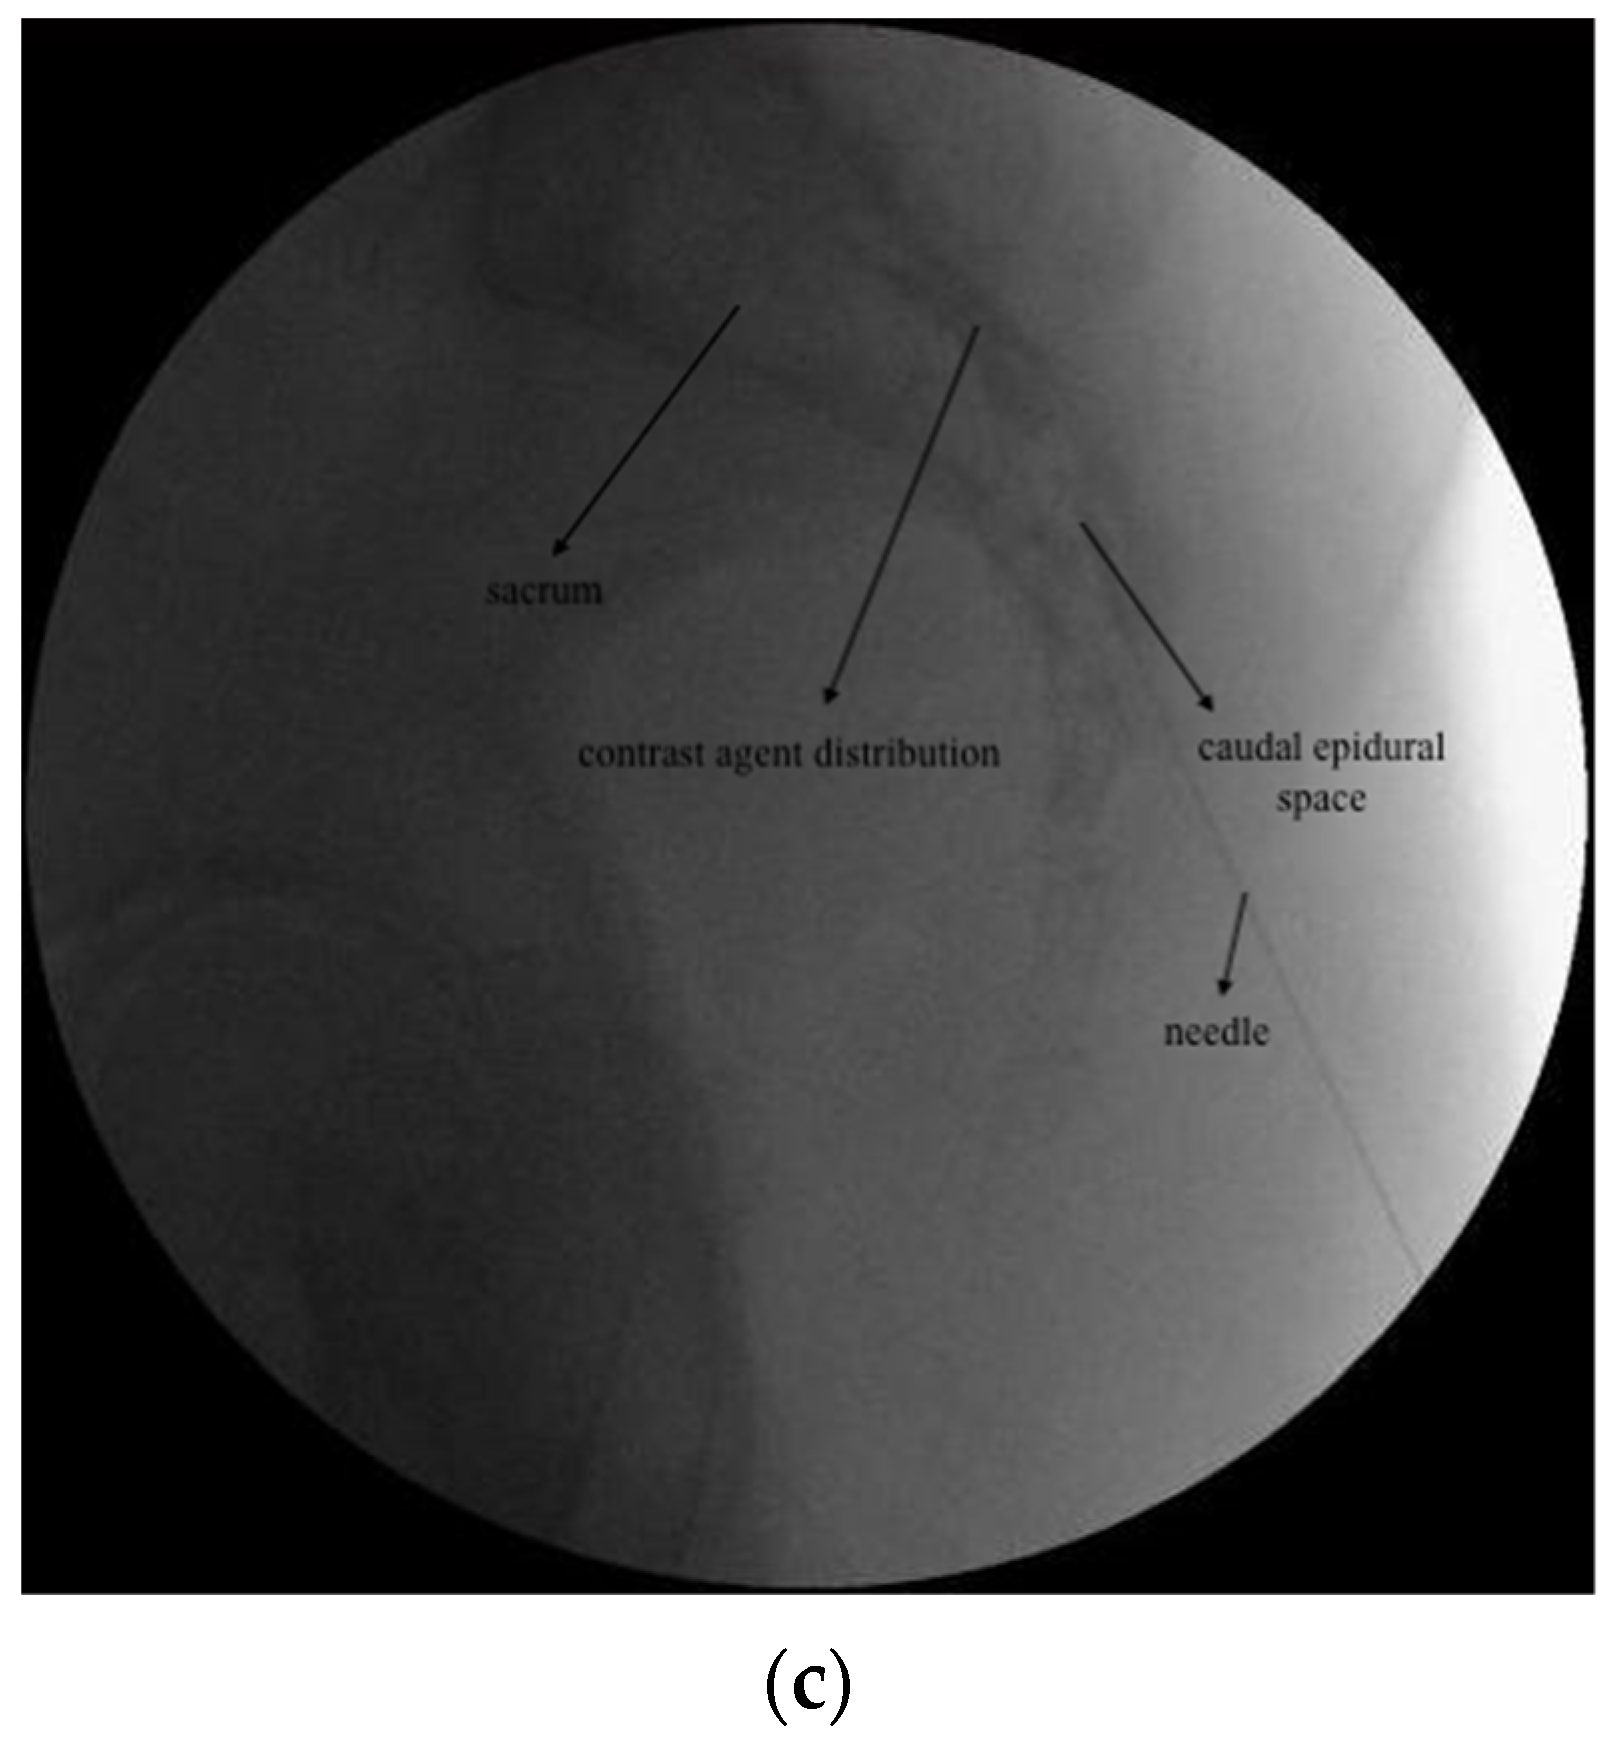

2.3.1. DRG PRF and TESI

2.3.2. CESI